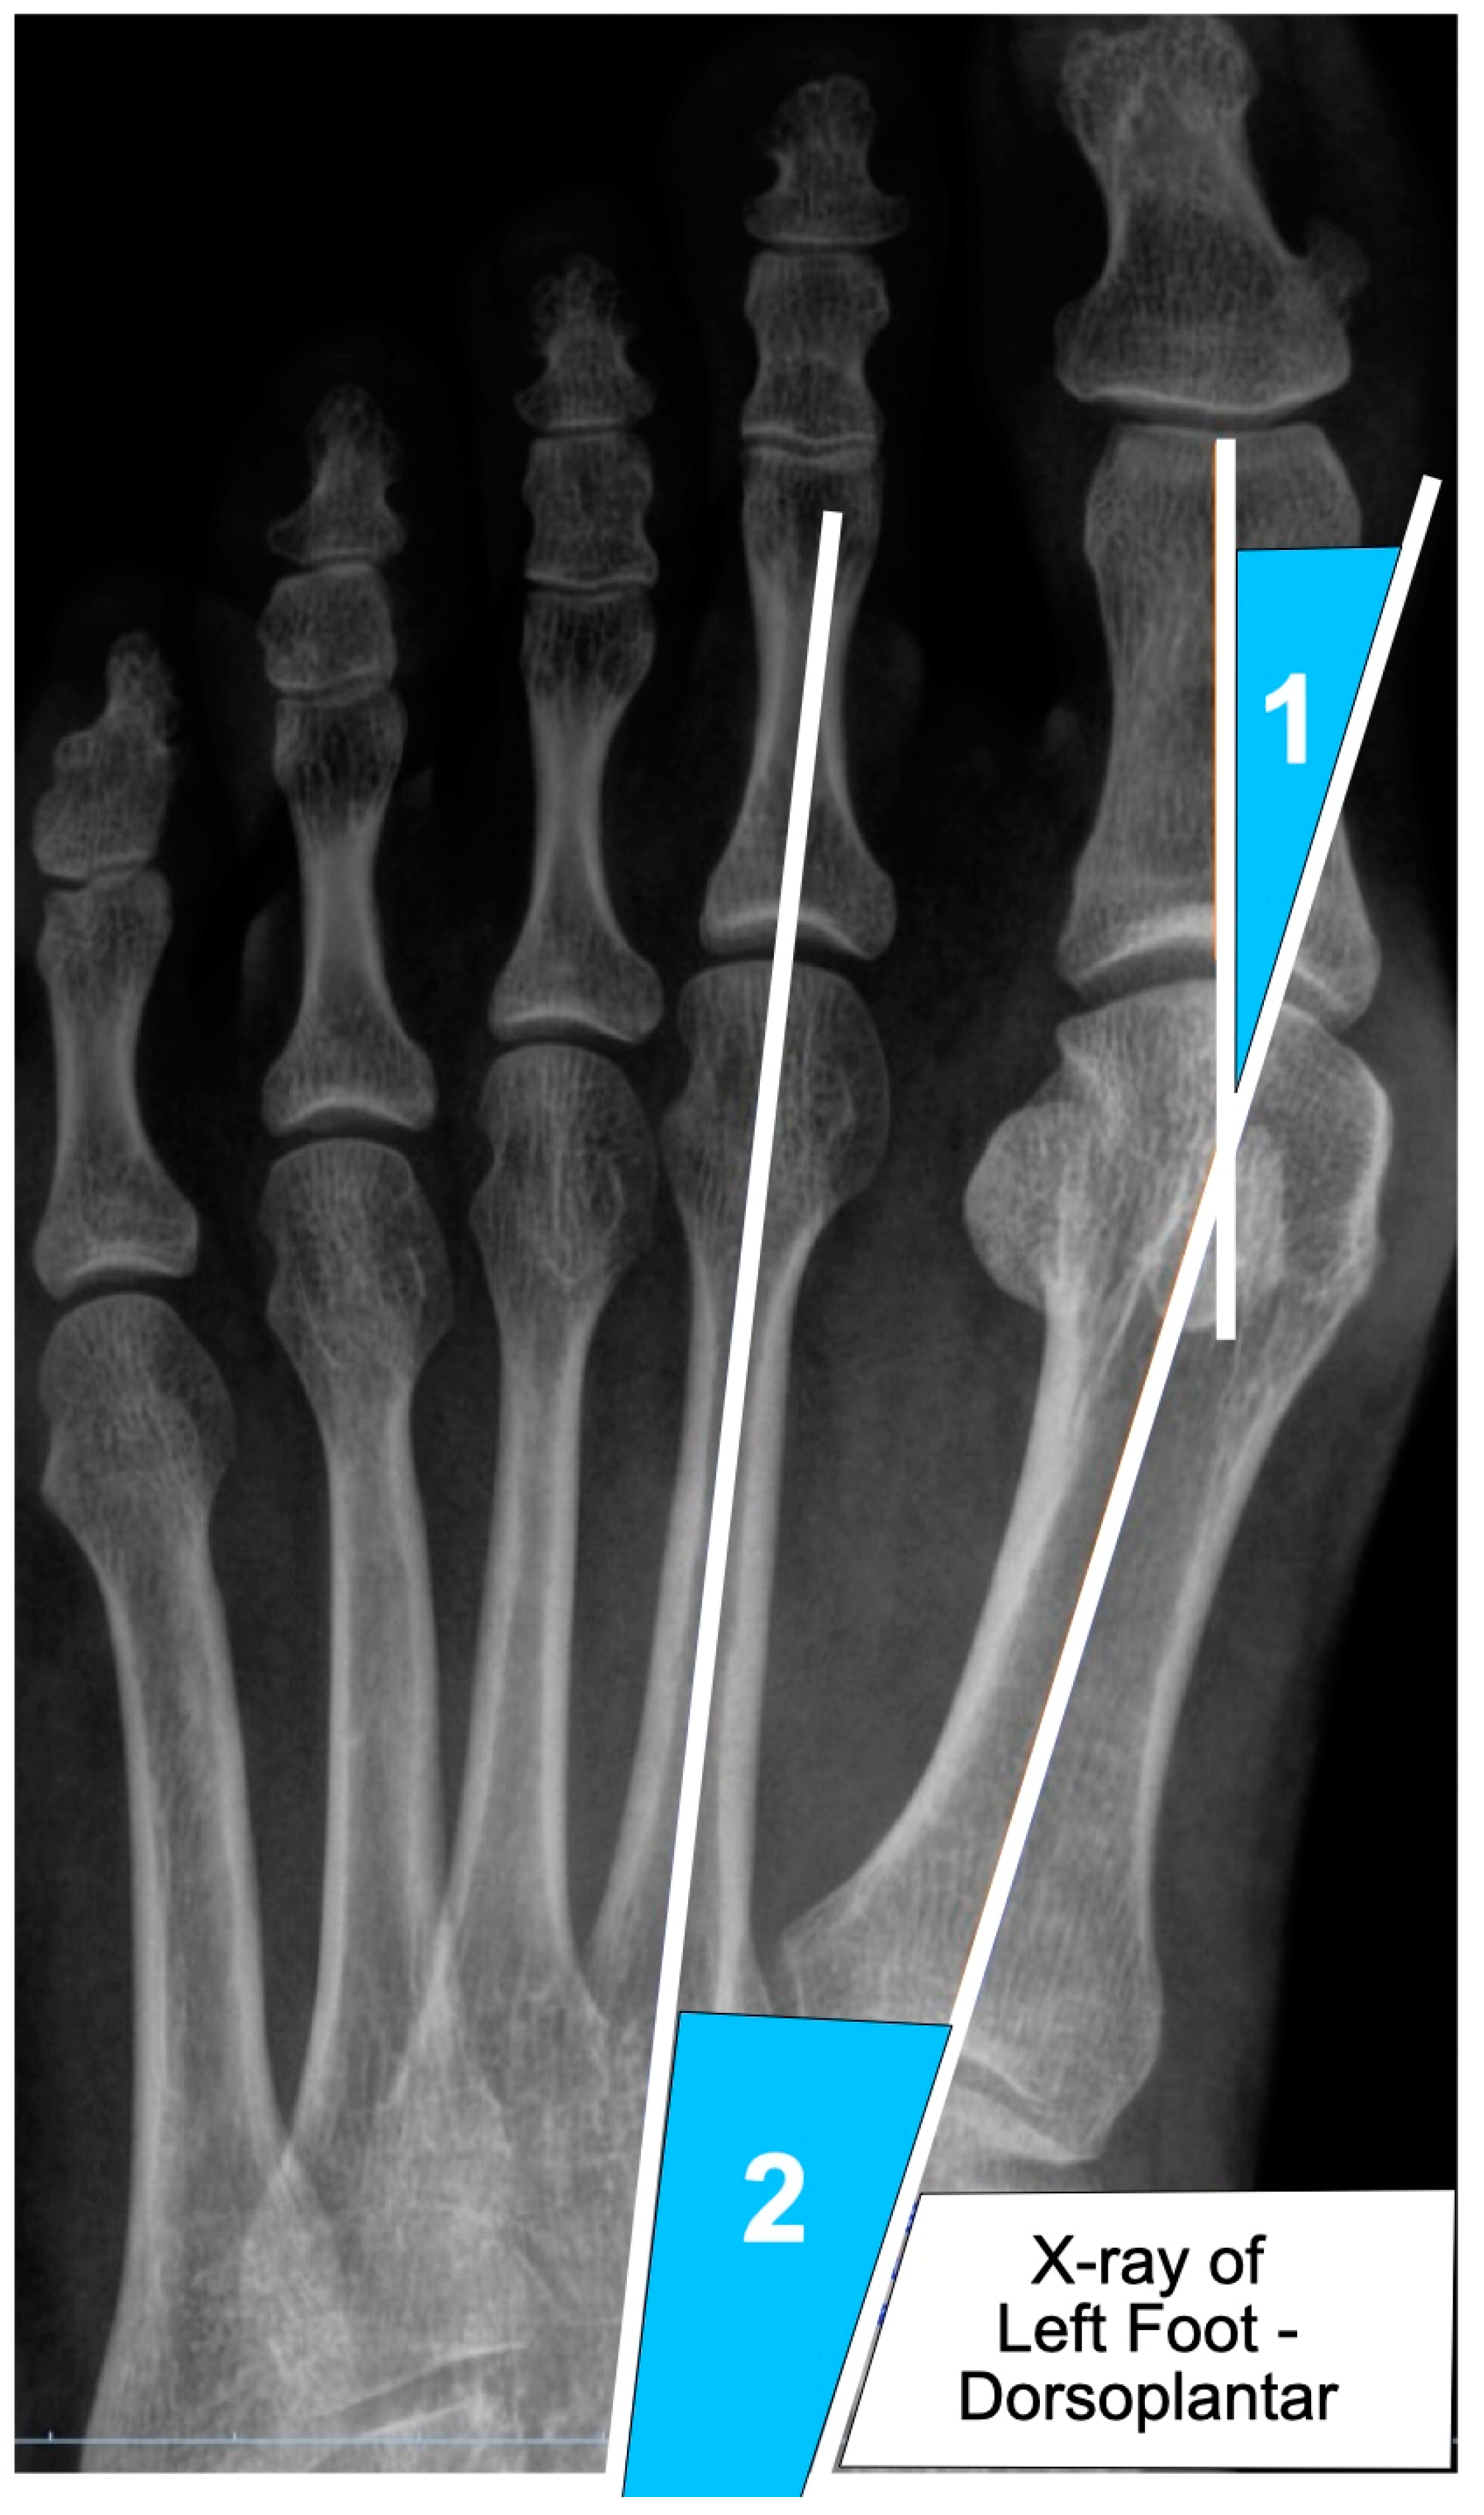

| HVA | Hallux Valgus Angle |

| IMA | Intermetatarsal Angle |